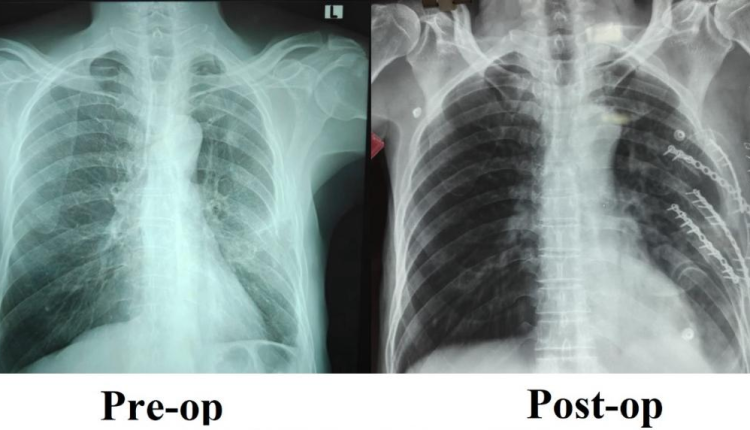

The patient, who had sustained multiple rib fractures in a road traffic accident, continued to suffer from severe chest pain for over a month despite optimal pain management and structured physiotherapy. The condition led to difficulty in deep breathing, disturbed sleep, and restricted daily activity due to poor healing and instability of the fractured ribs.

Recognising the need for surgical intervention, the trauma team led by Dr. Vijayan P, Associate Professor, Department of General Surgery, undertook a specialised rib fixation procedure to realign and stabilise the fractured ribs, enabling proper anatomical healing.

Following surgery, the patient showed rapid and marked improvement. Breathing became comfortable, mobility improved significantly with minimal pain, and the patient was able to resume routine activities with renewed confidence.